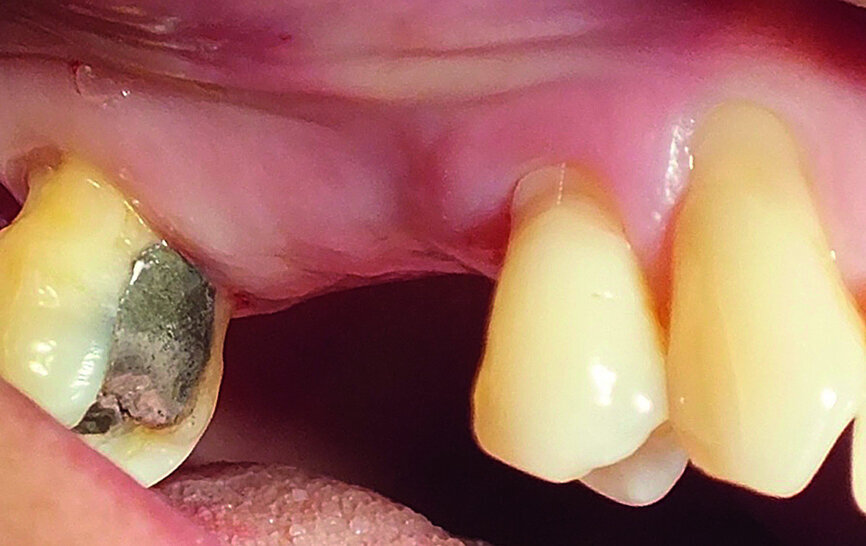

A 52-year-old female patient was concerned about the appearance of her smile. Her upper right first molar and second premolar had been missing for several years (Figs. 1 and 2). She was otherwise a fit and healthy non-smoker.

Fig. 1: The patient’s upper right first molar and second premolar had been missing for several years.